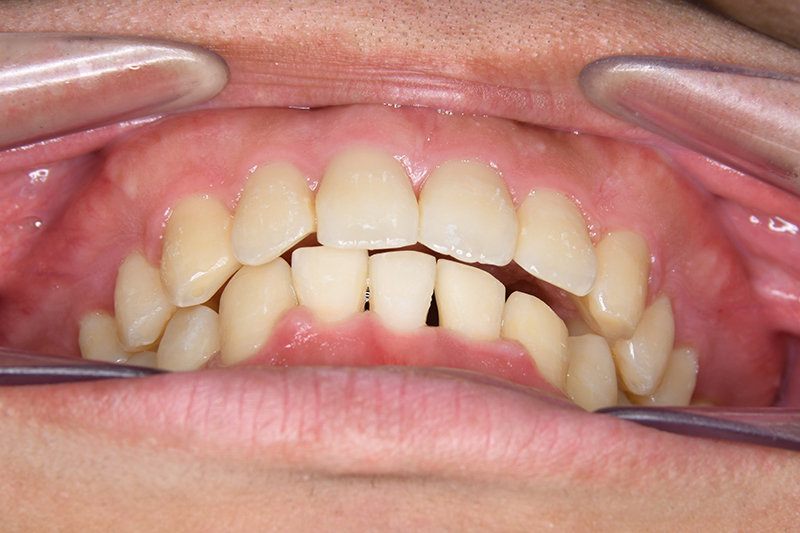

初診時

FP・IOP

主訴 物が噛みづらい 診断名 下顎右側側切歯先天欠如を伴う過蓋咬合症例

口腔内所見 over jet 8.5mm、over bite 6.0mm、下顎前歯先天欠如、右側臼歯関係I級、左側II級(end on)、上顎歯列弓はオーボイド型なのに対して、下顎は狭窄歯列、叢生歯列弓を呈しており左側は鋏状咬合となっていた。